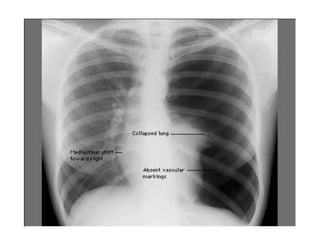

• Chest X-ray PA view showing the sharply

defined edge of the deflated lung with

complete translucency (no lung markings, no

vascular markings) between this and the chest

wall in the Rt side with shifting of

mediastinum to left.

• Suggestive of Rt Tension Pneumothorax

Pneumothorax

Collapsed Right Lung

Tension Pneumothorax: Requires chest tube

Tracheal Deviation